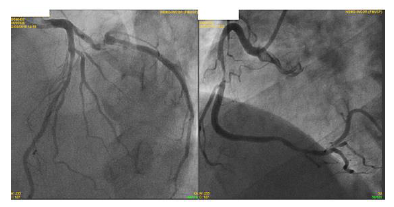

Durante a investigação, a paciente apresentou piora da angina, atualmente em CCS III e manteve-se refratária às medicações. Realizou o cateterismo (imagem abaixo).

I. Paciente apresenta lesão grave em artéria coronária direita e a revascularização percutânea dessa lesão pode ser realizada visando melhora de sintomas.

II. Paciente apresenta lesão em artéria coronária descendente anterior. O uso de métodos fisiológicos, como reserva de fluxo coronário (FFR) pode ser indicado para melhor avaliação e caso FFR menor que 0,8 a revascularização está indicado.

III. Em situações de lesões triarteriais, com acometimento de coronária descendente anterior (DA) em porção proximal, há indicação de revascularização. Deve-se calcular o Synthax escore e caso ele for maior que 32, há indicação de revascularização percutânea (via hemodinâmica) e caso menor que 32, há indicação de revascularização cirúrgica.